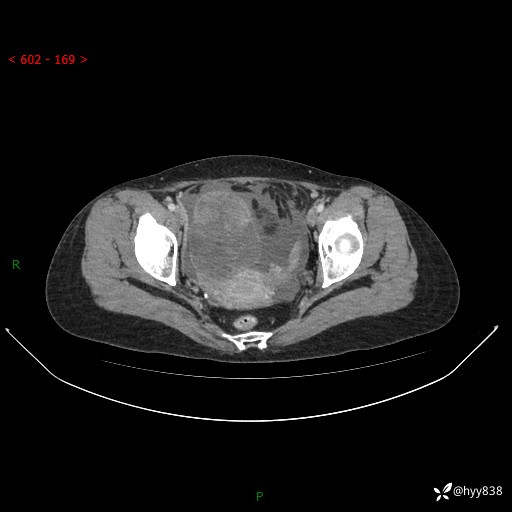

老年女性,尿频2月。超声发现盆腔囊实性占位,CT能否明确诊断---结果公布

现病史:患者绝经3-4年,期间无阴道出血及排液。患者近2月感尿频,自行口服中药治疗,症状无明显缓解。2024-4-25日于我院门诊就诊,行阴道彩超示:子宫肌瘤(大小约12*10mm,后壁),子宫右前方囊实性占位性病变(大小约126*82mm肿块声像,边界尚清,以无回声为主,可见范围约84*27mm稍高回声),内膜3mm。建议手术治疗。门诊以“卵巢囊肿”收入院。 病程中精神、食欲、睡眠可,大小便正常,体重体力无明显变化。

腹盆CT平扫

增强